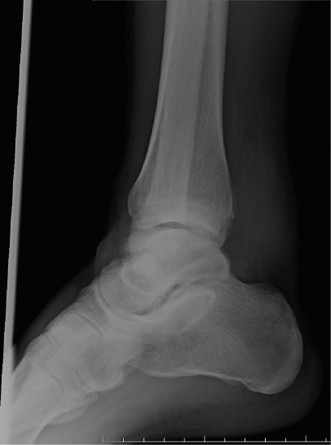

A 26-year-old man sustained an injury to his right ankle when he was caught in an avalanche while snowboardin…